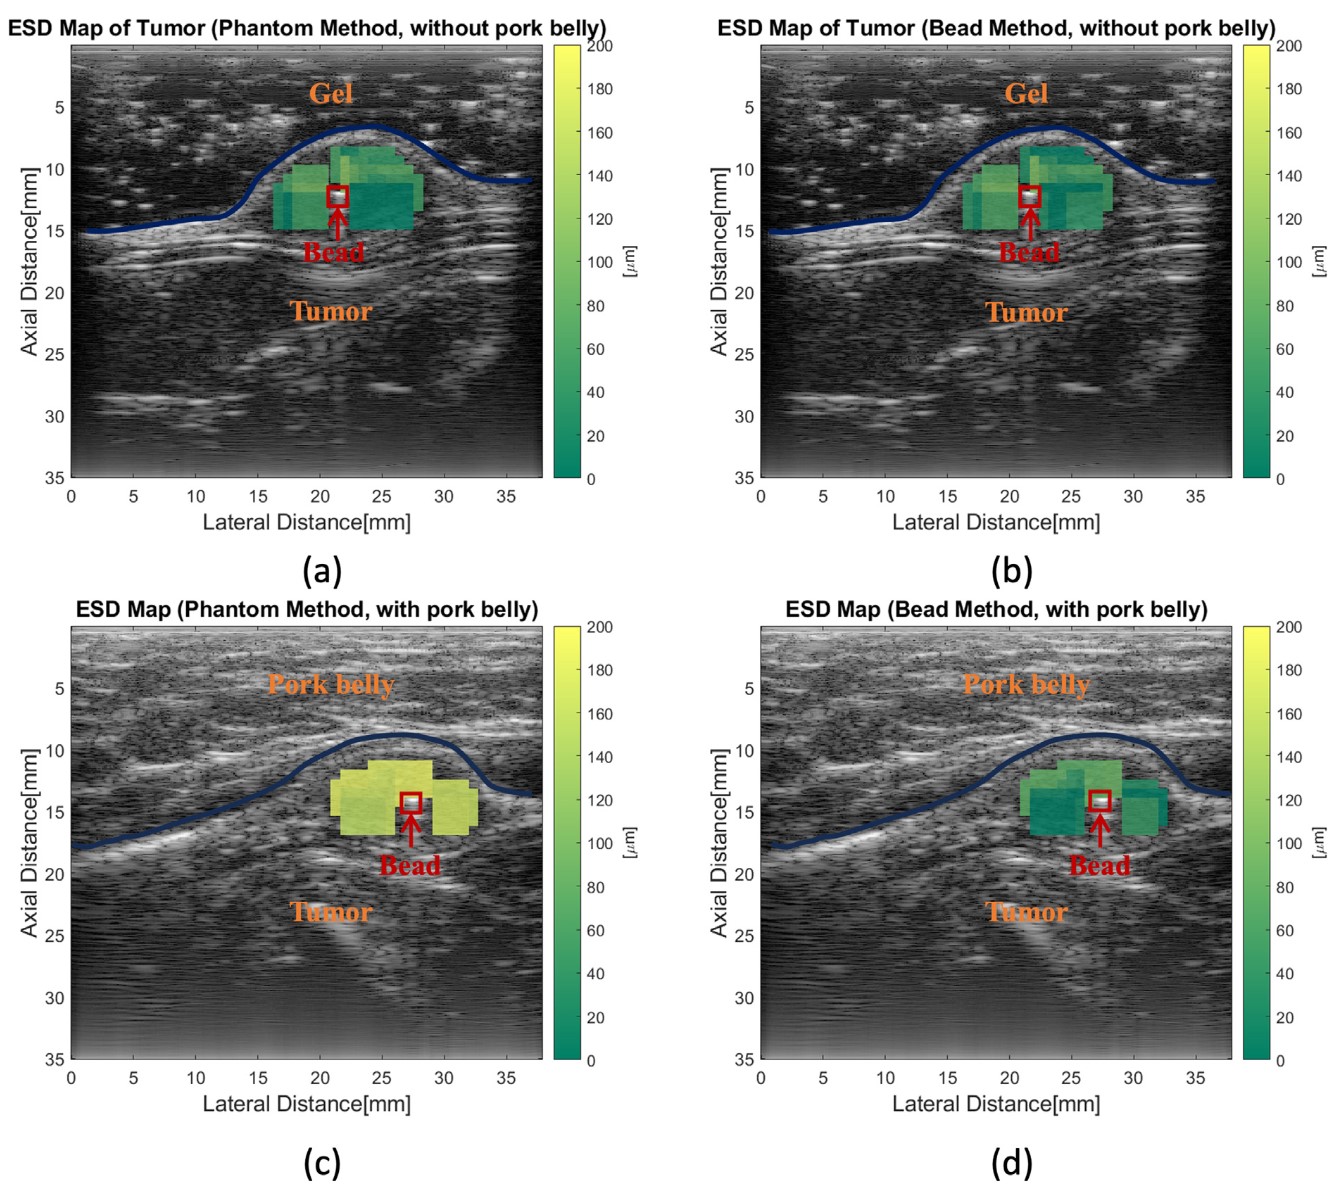

To further the analysis, they computed the equivalent scatterer diameter (ESD) and the effective acoustic concentration (EAC) by fitting a Gaussian model to the BSC curve. These parameters are helpful because they can bring some physical meaning to the BSC estimation. The next figure shows the mapping of the ESD in the same tumor in the 4 cases:

Equivalent scatterer diameter of a tumor using the reference phantom method and the bead method, with and without pork belly.

The estimations without pork belly were in good agreement. However, when the pork belly is added, a clear shift is seen in the ESD map of the RPM method. No apparent shift can be seen in the bead method.